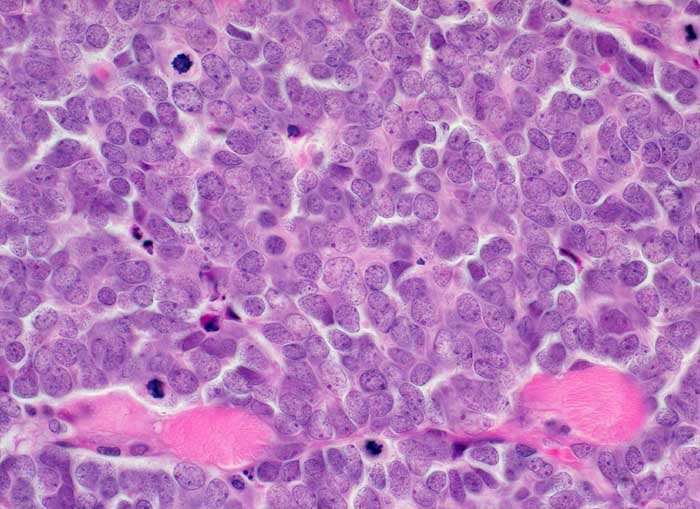

Merkel Zell Karzinom

Solides sehr monomorphes Tumorzellinfiltrat. Die Tumorzellen haben praktisch kein Zytoplasma. Das Chromatin ist fein granuliert. Die Kerne enthalten feine Nukleolen. Zahlreiche Mitosen. Der Tumor infiltriert die Skelettmuskulatur.

Immunhistochemie: CK20 und Synaptophysin positiv. Melanommarker, CD20, CD45, TTF1 negativ.

Tumor am Unterlid

400